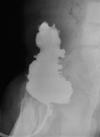

Striated Nephrogram:

Case courtesy of Dr David Cuete, Radiopaedia.org, rID: 28077

Imaging demonstrates preserved renal parenchyma perfusion, but with minimal or absent excretion into the urinary collecting system.

Imaging with iodinated contrast typically demonstrates an immediate or mildly delayed nephrogram, but without excretion into the collecting system. Delayed 24 hour imaging would also demonstrate persistent nephrogram or striated nephrogram due to stasis of contrast within the renal tubules 3,4.